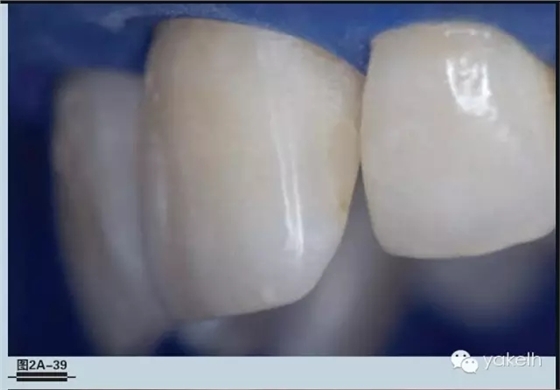

圖2A-39和2A-40-修復(fù)過(guò)程完成后即刻觀察。需要注意的是因?yàn)樘烊谎赖拿撍?,修?fù)體表現(xiàn)比牙齒組織暗。

圖2A-41-3天后查看修復(fù)體。注意牙齒脫水恢復(fù)正常,修復(fù)體幾乎看不出來(lái)。記住,沒(méi)有進(jìn)行預(yù)備斜面